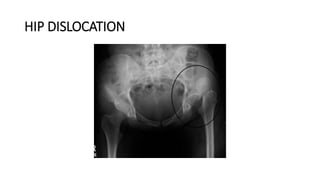

HIP DISLOCATION

DEFINITION

• Occurs when the head of the thighbone (femur) is forced out of its

socket in the hip bone (pelvis).

• It typically takes a major force to dislocate the hip. Car collisions and

falls from significant heights are common causes and as a result,

other injuries like broken bones often occur with the dislocation.

• A hip dislocation is a serious medical emergency. Immediate

treatment is necessary.

(Left) This x-ray, taken from the front, shows a patient with a posterior dislocation

of the left hip. (Right) Normal alignment after the hip has been reduced.